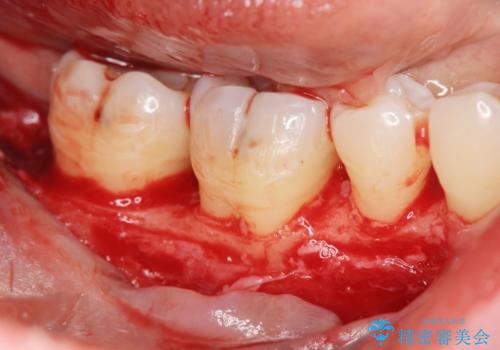

歯を抜かずに残せるよう、再生療法・歯周ポケット除去手術を計画します。

再生治療を行うことで、吸収した骨を再生し歯を保存できることがあります。

- 外科手術のため、術後に痛みや腫れ、違和感を伴います